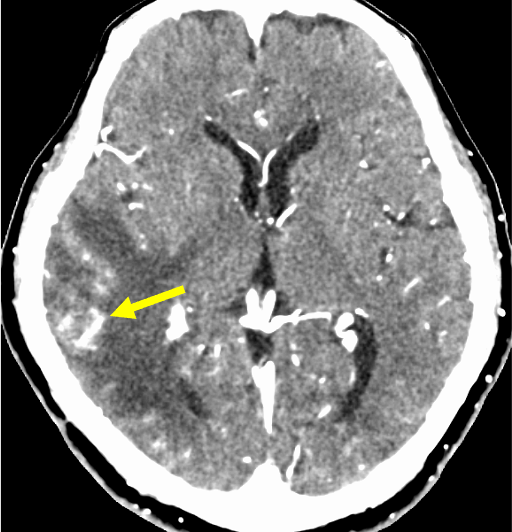

図2.造影CT動脈相

病変は軽度増強効果あり。この時相からCT angiographyのMIP像やVR像を作成した。